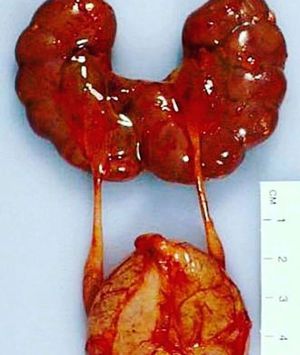

Horseshoe kidney

Also known as Ren Arcuatus (in latin), is a congenital disorder more common in males. The kidneys fuse together during the development in the womb and form a horseshoe-shaped renal fusion or super kidney.